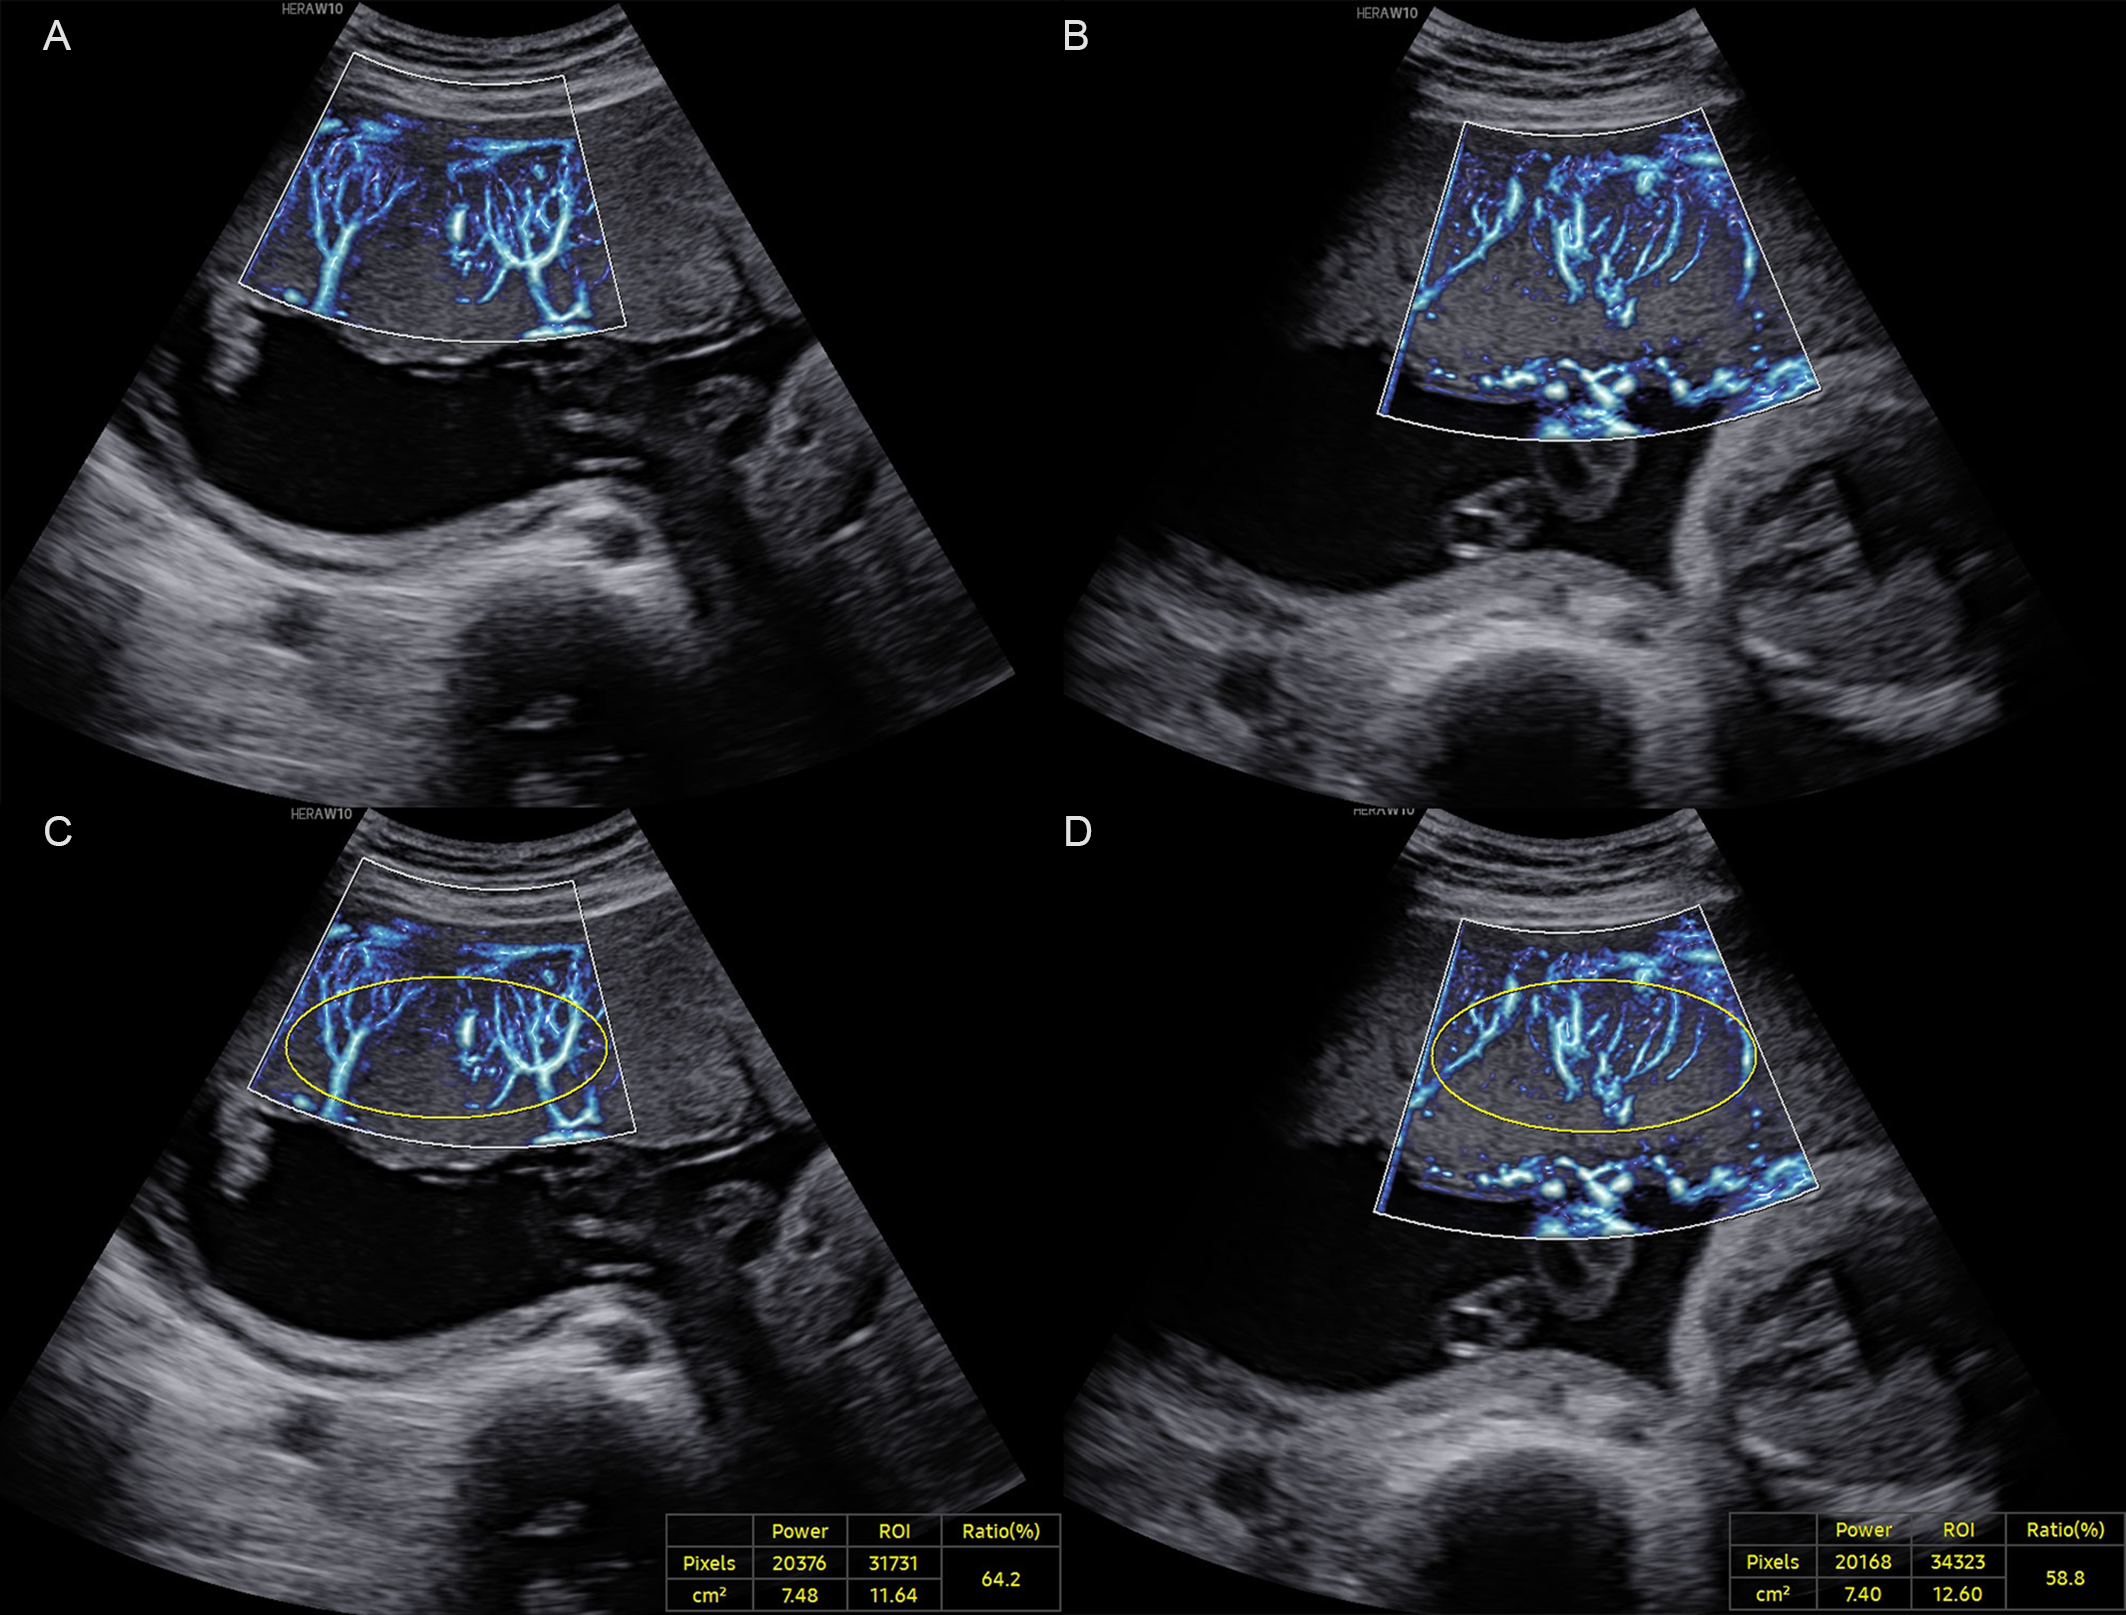

The placenta was divided into middle and peripheral regions along the longitudinal axis, with the middle segment corresponding to the middle third of the placenta along its axis, and the peripheral segment comprising the remaining portion [20]. MV-Flow imaging was performed three times in both the middle and peripheral placental segments, yielding three separate VIMV measurements per region. The mean of three measurements per region was calculated and recorded as VIMV-middle (VIMV-m) or VIMV-peripheral (VIMV-p) (Fig. 1).

Fig. 1. A normal pregnancy case at 27+6 weeks of gestation. (A) MV-Flow imaging of the peripheral segment of the placenta along the longitudinal axis. (B) MV-Flow imaging of the middle segment. (C) Vascular index (VIMV) for the peripheral segment (VIMV-p, 64.2%). (D) VIMV for the middle segment (VIMV-m, 58.8%). ROI, region of interest; MV-Flow, microvascular-flow. The yellow circle shows the ellipse-shaped region of interest for which the VIMV was calculated.